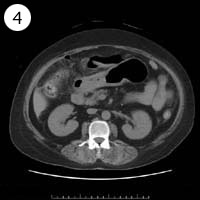

57歳 女性

異常のある4枚組は?

単純CT